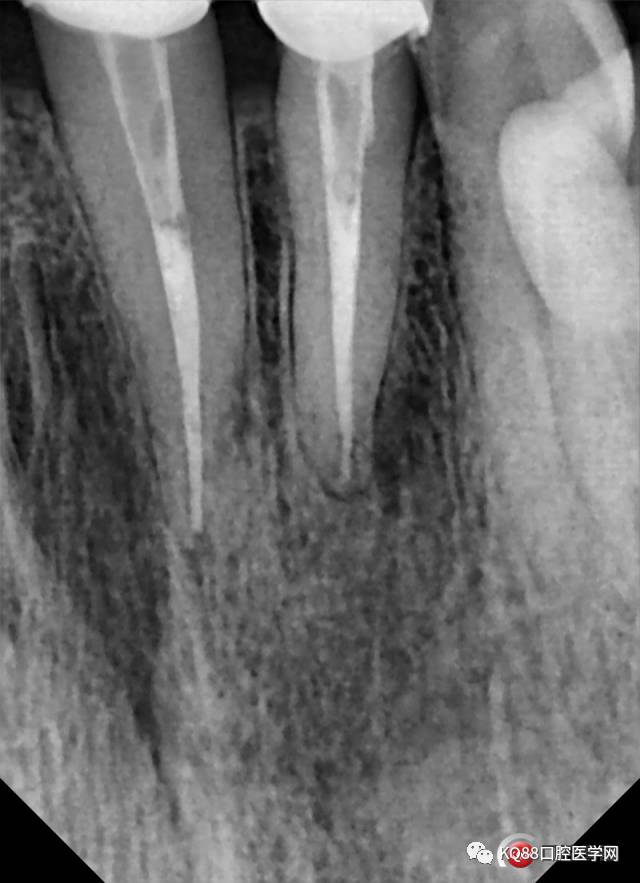

根管治疗完善后,过了一个月患者瘘管没有再复发就修复了,然后以为就没有然后了,结果今天3月30日患者来突然说瘘管又有点溢脓了,之前跟她沟通过再有溢脓就要行根尖手术:

还是根尖偏远中的地方有一点,但是明显感觉比第一次全景时范围小了,好了开始准备根尖手术,